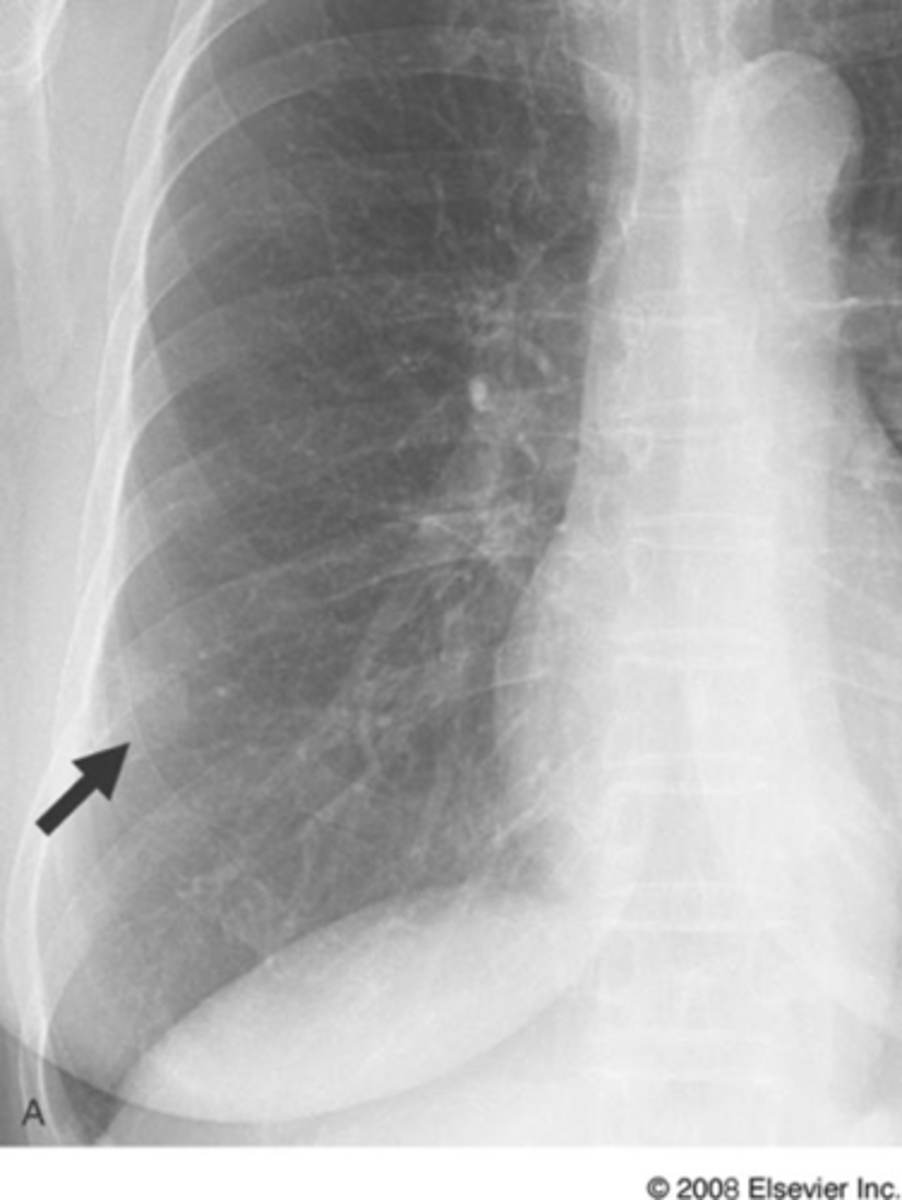

spine sign

vertebral bodies are lighter (white) than normal on lateral x-ray view

spine sign